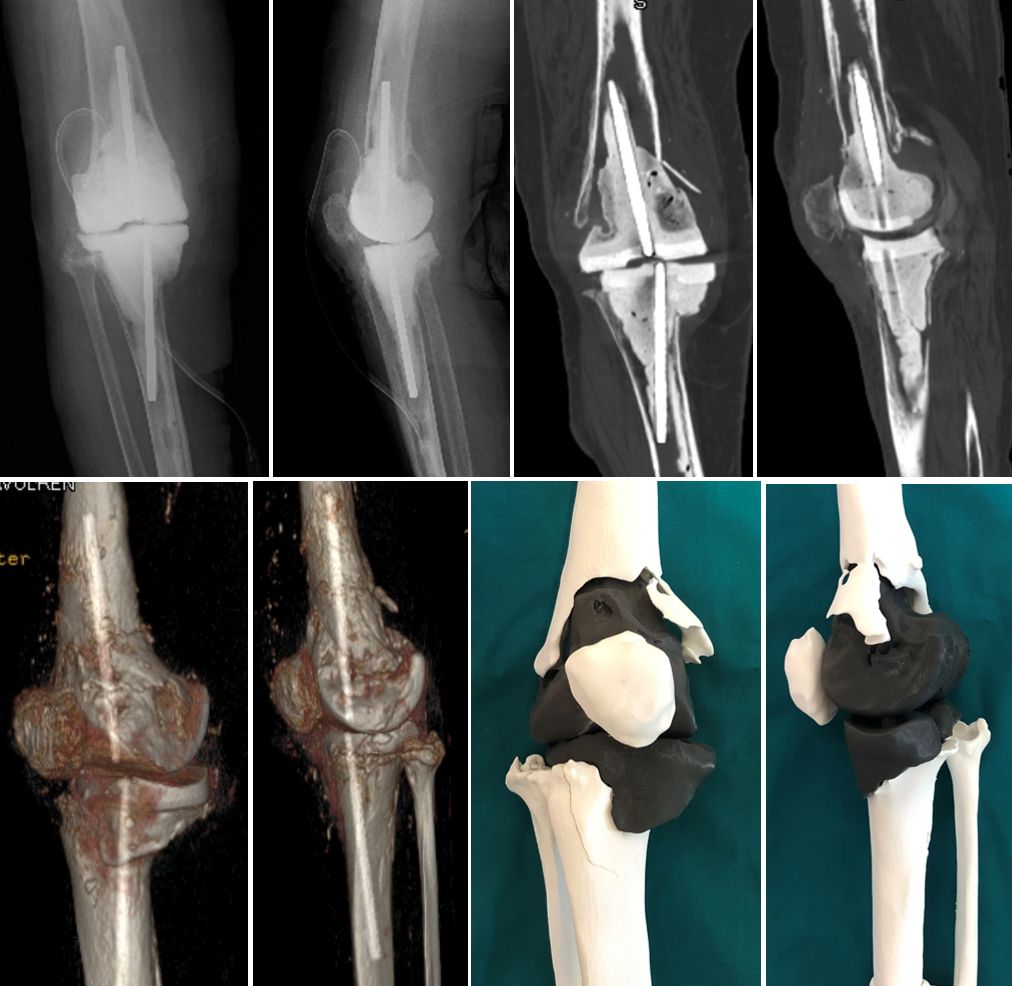

The development of three-dimensional (3D) printing technology is proposed for better planning of complex revision surgery. Regarding preoperative revision planning, conventional radiographs often underestimate the degree of bone loss, while computed tomography (CT) can provide additional details, but the surgeon is limited in his or her ability to clinically translate this information into surgical execution (Fig. 1).

3D technology has already been used for complex hip revisions in our department for many years. In a recent published study we compared the diagnostic accurracy between 3D printed model with 3D CT reconstruction for pelvic discontinuity [19] (Fig. 2). For knee revision surgery based on a preoperative CT scan, a 1:1 3D plastic knee model is made, including the cement spacer or implant to be removed in a different colour and separated from the virtual bone (Fig. 3).

Images in DICOM format (Fig. 4) were processed by using M3DICS medical grade software (www.medics3d.com).

The first step is the image processing that provides a 3D virtual model (HA3D™ reconstruction) of the knee, based on high resolution CT scans. It focuses on the reconstruction of bone structures outside the spacer and/or implants. The next step is the printing of the HA3D™ mathematical model into the correlated interactive 3D PDF allowing navigation (Fig. 5).

With the HA3D™ model, a complete case report with all relevant measurements is provided. After the validation of the printed project, the model is produced with additive manufacturing technology, in particular FDM (Fused Deposition Modeling) technology. PLA (Polylactic Acid) material is the most commonly used for 3D models (Fig. 6-8).